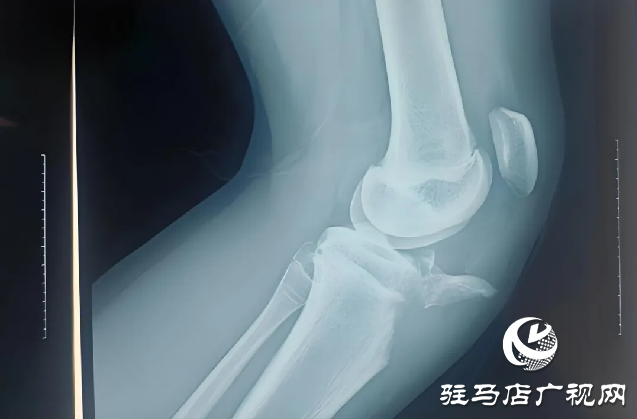

近日,胡同學(xué)在學(xué)校上樓梯時不慎摔倒,傷后感到左膝疼痛不適,活動不能,家人緊急送他來駐馬店市第一人民醫(yī)院骨科二病區(qū)。入院后完善相關(guān)檢查,任耀醫(yī)生根據(jù)胡同學(xué)的病情、影像學(xué)、術(shù)前檢查,做出診斷:左脛骨結(jié)節(jié)撕脫性骨折;左髕韌帶斷裂。

駐馬店市第一人民醫(yī)院任耀醫(yī)生提醒,脛骨結(jié)節(jié)撕脫骨折屬運動損傷,較少見,好發(fā)于12-17歲男性青少年。損傷機制為股四頭收縮(向心,離心)牽拉致傷,常見于加速跑,起跳,落地等發(fā)力瞬間,根據(jù)X線片骨折線走行及移位情況分為3型。臨床表現(xiàn)為疼痛,主動伸膝行走、負重不能,X線可見脛骨結(jié)節(jié)骨折,髕骨上移,有時可合并髕腱斷裂。